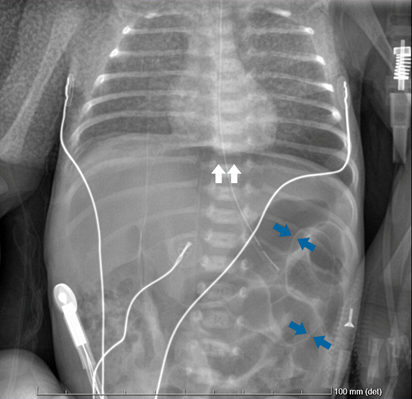

Question :A male infant born at 31 weeks and 6 days of gestation by vaginal delivery with a birth weight of 1785 g had Apgar score of 8 and 9 at 1 and 5 minutes, respectively. The mother's routine prenatal evaluation was unremarkable and she had completed a course of corticosteroid therapy. The infant needed oxygen supplementation and was started on empirical antibiotics with intravenous (IV) ampicillin and gentamicin. Minimal enteral nutrition with breast milk was started from second day of life which was gradually increased. On day 6 of life, he needed nasal continuous positive airway pressure due to nosocomial sepsis. Antibiotics were changed to IV vancomycin and cefotaxime; feeding was stopped, and umbilical line was removed. Two days later, he had further clinical worsening with abdominal distension and decreased bowel sounds. Laboratory studies showed increased inflammatory markers (C reactive protein 24.9 mg/dL) with leucopenia (white cell count 4000/cumm). Chest and abdominal radiographs revealed signs of pneumoperitoneum, including Rigler's sign (Figure 1). An exploratory laparotomy revealed a perforation and necrosis of the cecum, ascending and transverse colon.

Figure 1. Supine radiograph of the abdomen showing the presence of air on both sides of the bowel wall (blue arrows) and infra-diaphragmatic air (white arrows)  What is Rigler's sign?

In Rigler's sign, also known as bas-relief or double wall sign, both the outer and inner walls of the bowel wall can be visualized when there is air present within the peritoneal cavity and the intestinal lumen. 1,2,3,4 It is the second most common sign of pneumoperitoneum, 1 seen in 14-32% of the cases. 4 Presentation of this sign requires larger volume of gas and is seen most frequently in colonic and gastric perforations. 4 A Rigler's sign variant occurs when only the outside of the bowel wall is visible because the lumen is filled with fluid. 2,3

Optimal radiographic technique is important with a suspected abdominal perforation and at least two radiographs (a supine and a lateral decubitus in neonates) should be obtained. If Rigler's sign is believed to be present, an ultrasound or a computed tomography should be performed as well as a surgical consultation obtained. 1 Early diagnosis and appropriate treatment may be lifesaving. | References : | - Sanchez Arroyo ND, Solano JJ. Rigler Sign. [Updated 2020 Aug 16]. In: StatPearls [Internet]. Treasure Island (FL): StatPearls Publishing; 2020 Jan. Available from: https://www.ncbi.nlm.nih.gov/books/NBK539847/